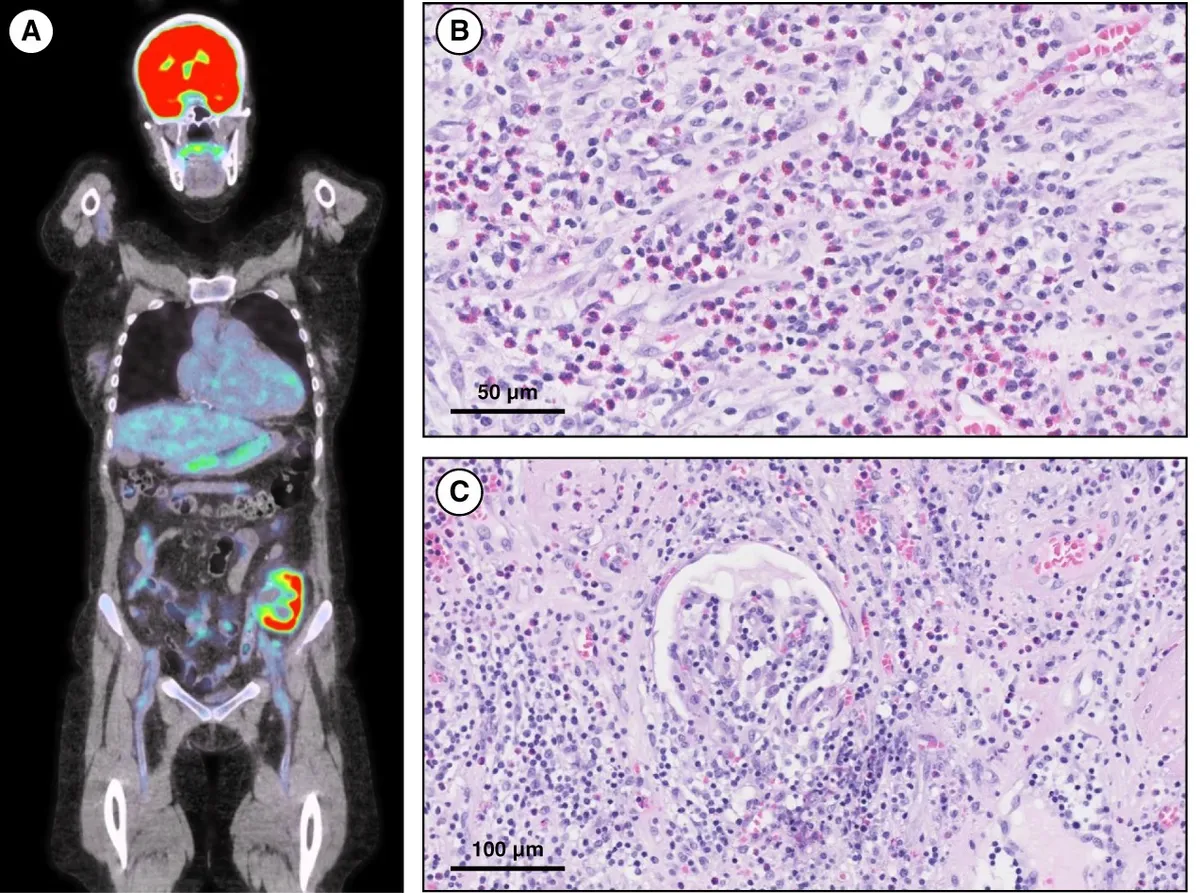

Foi realizado PET-CT que demonstrou atividade metabólica intensa no córtex do enxerto renal, sugerindo um quadro de rejeição aguda.

A biópsia do enxerto evidenciou inflamação intersticial significativa com infiltração por eosinófilos e linfócitos, glomerulite severa (g3), capilarite peritubular (ptc3) e contornos duplos na membrana basal glomerular (cg1). A coloração C4d foi positiva, confirmando rejeição mediada por anticorpos crônica ativa rica em eosinófilos.